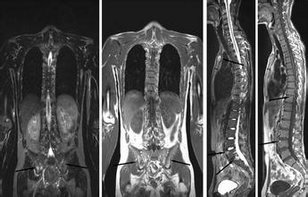

CT/X片/MRI等